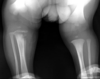

Fratura do platô tibial lateral - Schatzker tipo 2 (traço de fratura + depressão do plato lateral).